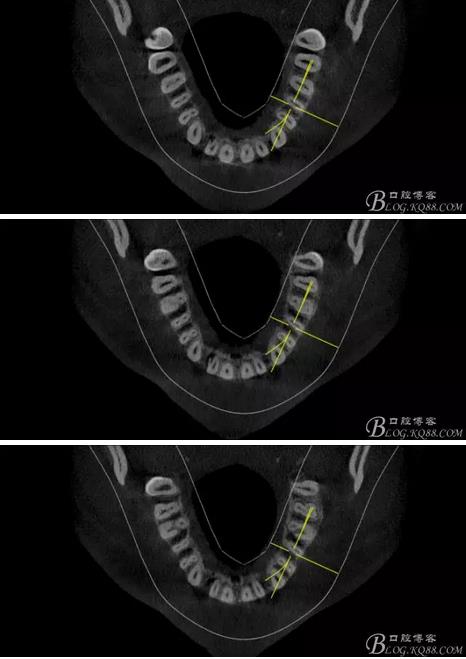

(1) 檢查:12唇側(cè)牙齦可見竇道,牙體顏色較鄰牙暗,無光澤,形態(tài)完整無缺損,唇側(cè)及近遠中向未提及牙周袋。腭側(cè)齦緣輕度紅腫,舌側(cè)窩可探及裂溝,可見浸墨狀痕跡,沿裂溝舌側(cè)探診牙周袋深大于11mm,除患牙外全口牙周狀況良好,為探及牙周袋,牙齦色粉紅。邊緣菲薄,質(zhì)地堅韌。12冷熱診無反應,叩診(+-),無明顯松動,無咬合創(chuàng)傷。12根尖x線片示,根管中三分之一中可見一斜向線樣透射影像根尖區(qū)及遠中根三分之一可見低密度透射暗影,錐形束CT示12根尖區(qū)唇腭向骨吸收已穿通,根面溝達根中三分之一卷曲分出另一牙根,再未見其他明顯的根管系統(tǒng)。